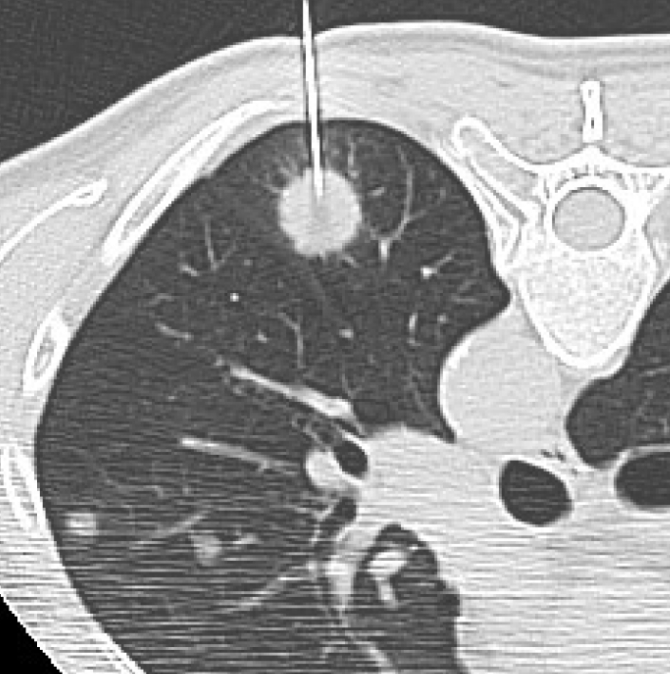

폐 편평세포암은 폐암의 한 유형으로, 주로 흡연과 관련이 있습니다. 기침이 3주 이상 지속되거나 피 섞인 가래, 숨이 차는 증상이 있으면 검사를 받아야 합니다. 흡연자는 비흡연자보다 편평세포암 발생 위험이 몇 배나 높습니다. 금연은 가장 강력한 예방책이며, 폐 건강을 지키는 가장 직접적인 방법입니다.

진단은 흉부 X선, CT, 기관지 내시경, 조직검사로 이뤄집니다. 치료는 수술, 방사선, 항암치료, 면역치료가 병합됩니다. 최근에는 맞춤형 치료제가 도입되어 생존율이 향상되고 있습니다.